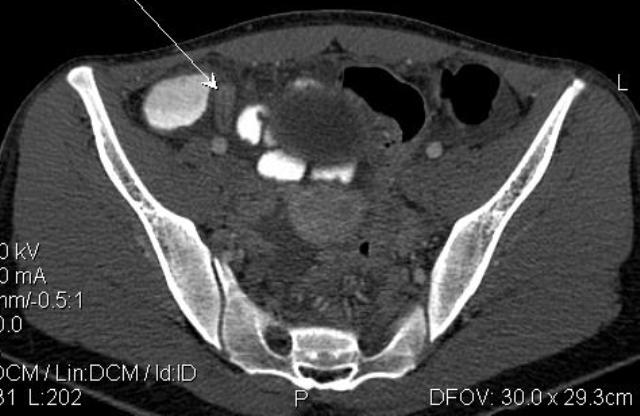

Диагностика острого аппендицита по УЗИ: очень актуальная тема; УЗ аппараты практически есть во всех клиниках; метод доступный и не сложный; главное владеть правильной техникой. Не буду загружать лишней теорией и разными ссылками; поделюсь практическим опытом. У меня линейный датчик 3-12 мегагерц с плавающей частотой; аппарат Филипс HD 11, всегда включаю соно-КТ (9800 цифровых каналов) и гармонику когда смотрю кишечник. Нормальный аппендикс видеть можно; но вопрос зачем??? Как правило, если при наличии достаточного опыта аппендикс не виден; значит скорей всего аппендицита нет. Когда "идешь" на аппендицит то главное по началу набраться терпения и......хорошая компрессия! По началу надо минут 10-15; потом когда появится достаточный опыт; за 2-5 минут можно справится и получить отличную визуализацию. Мочевой пузырь лучше опорожнить; часто он приподнимают тонкий кишечник и может закрыть "окно" через которое будет видно апендикс. Сначала находим слепую кишку потом находим илео-цекальное соединение;

после начинаем производить хорошую компрессию датчиком попрося пациента сообщить в какой точке боль наиболее выражена; медленными движениями датчика сканируем область наибольших болевых ощущений и как правило находим утолщенный отросток. Лучше начинать с поперечной визуализации и идти к верхушке аппендикса что бы убедится что это аппендикс и он заканчивается, а не тонкая кишка (которая если и закончится то только переходя в слепую); потом надо аккуратно развернуть продольно датчик и посмотреть от верхушки аппендикса к слепой. Норма диаметра: 3-4 мм; 5-6 мм под вопросом (клиника решает; но я в катаральный аппендицит не верю); 7-8 мм и больше, не компремируемый (фиксированный отросток)-острый аппендицит! Помимо наличие утолщенного аппендикса; признака "бычьего глаза" (bull-eye sign) при поперечном сканировании; надо обращать внимание на присуствие аппендоколитов в просвете; деструкцию стенки и свободной жидкости в зоне интереса.